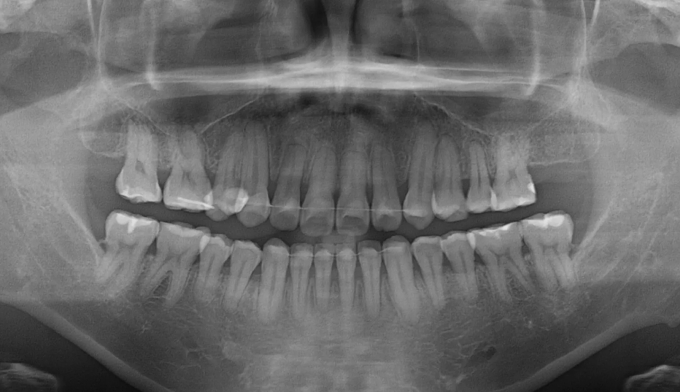

어금니가 상실된 경우, 보통 해당공간에 임플란트를 식립합니다. 하지만 보철치료에 대한 거부감이 있거나, 그 폭이 애매하게 좁은 경우, 교정치료를 통해 공간을 닫는것이 효과적인 경우가 많습니다.

해당 케이스에서는 반대쪽 어금니도 없었기 때문에 짝을 맞추기 위하여 임플란트 식립 대신 해당 공간을 교정치료를 통해 닫기로 하였습니다.

9개월만에 2개의 어금니를 전방으로 이동시켜 아래 어금니와 안정적인 교합을 형성하였습니다. 임플란트 없이 본인의 치아로 불편함없이 지낼 수 있게 되었습니다.